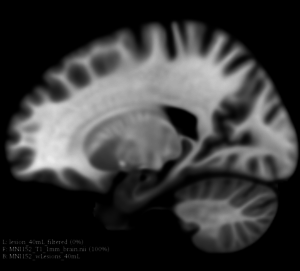

This extension offers a set of tools for brain lesion simulation, based on MRI images. At the moment, the module MS Lesion Simulator is available, where it can simulate both baseline scan lesion volumes (given a lesion load) and longitudinal image simulations. In summary, a statistical lesion database is generated based on a set of manual lesion mark-ups, being non-linearly registered to MNI152 space (isotropic 1mm of voxel resolution), and a local contrast ratio is applied on each imaging modality provided by the user. Using a small set of parameters (lesion load, lesion homogeneity, lesion intensity independence and lesion variability), it is possible to generate a broad range of MS lesions patterns in multimodal MRI imaging techniques (at moment, T1, T2, T2-FLAIR, PD, DTI-FA and DTI-ADC images are provided). For more details about this project, please see the original paper.